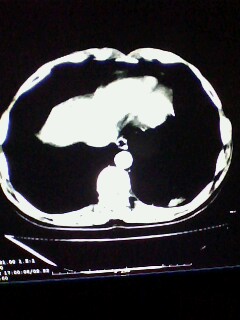

标题: CT28315:咳嗽咳痰咯血半月并胸痛 [打印本页]

标题: CT28315:咳嗽咳痰咯血半月并胸痛

左下肺肿块影,深分叶,考虑肺癌。

左下肺球形病灶,考虑:1:球形肺炎;2:周围型肺癌不除外,建议治疗后复查

不排除左肺下叶周围型肺癌可能!建议穿刺活检!